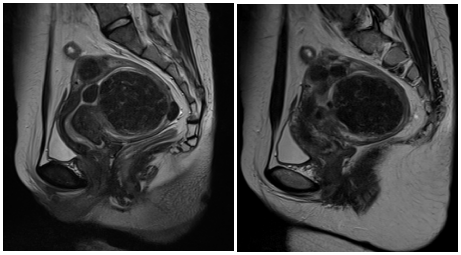

海扶刀手术帮子宫肌瘤患者轻松灭瘤海扶刀手术治疗案例2016年,陈女士(化名)体检时发现子宫肌瘤,因自觉无症状,且听人说子宫肌瘤等到绝经后就会缩小不会再生长,并没有在意只是定期到医院复查。2018年,陈女士出现月经量增多,比平素月经量增多1/3,伴有血块,周期与经期正常,偶有痛经,便四处求医。医生建议手术治疗,但出于对手术的恐惧和害怕疼痛,陈女士心里无比纠结,